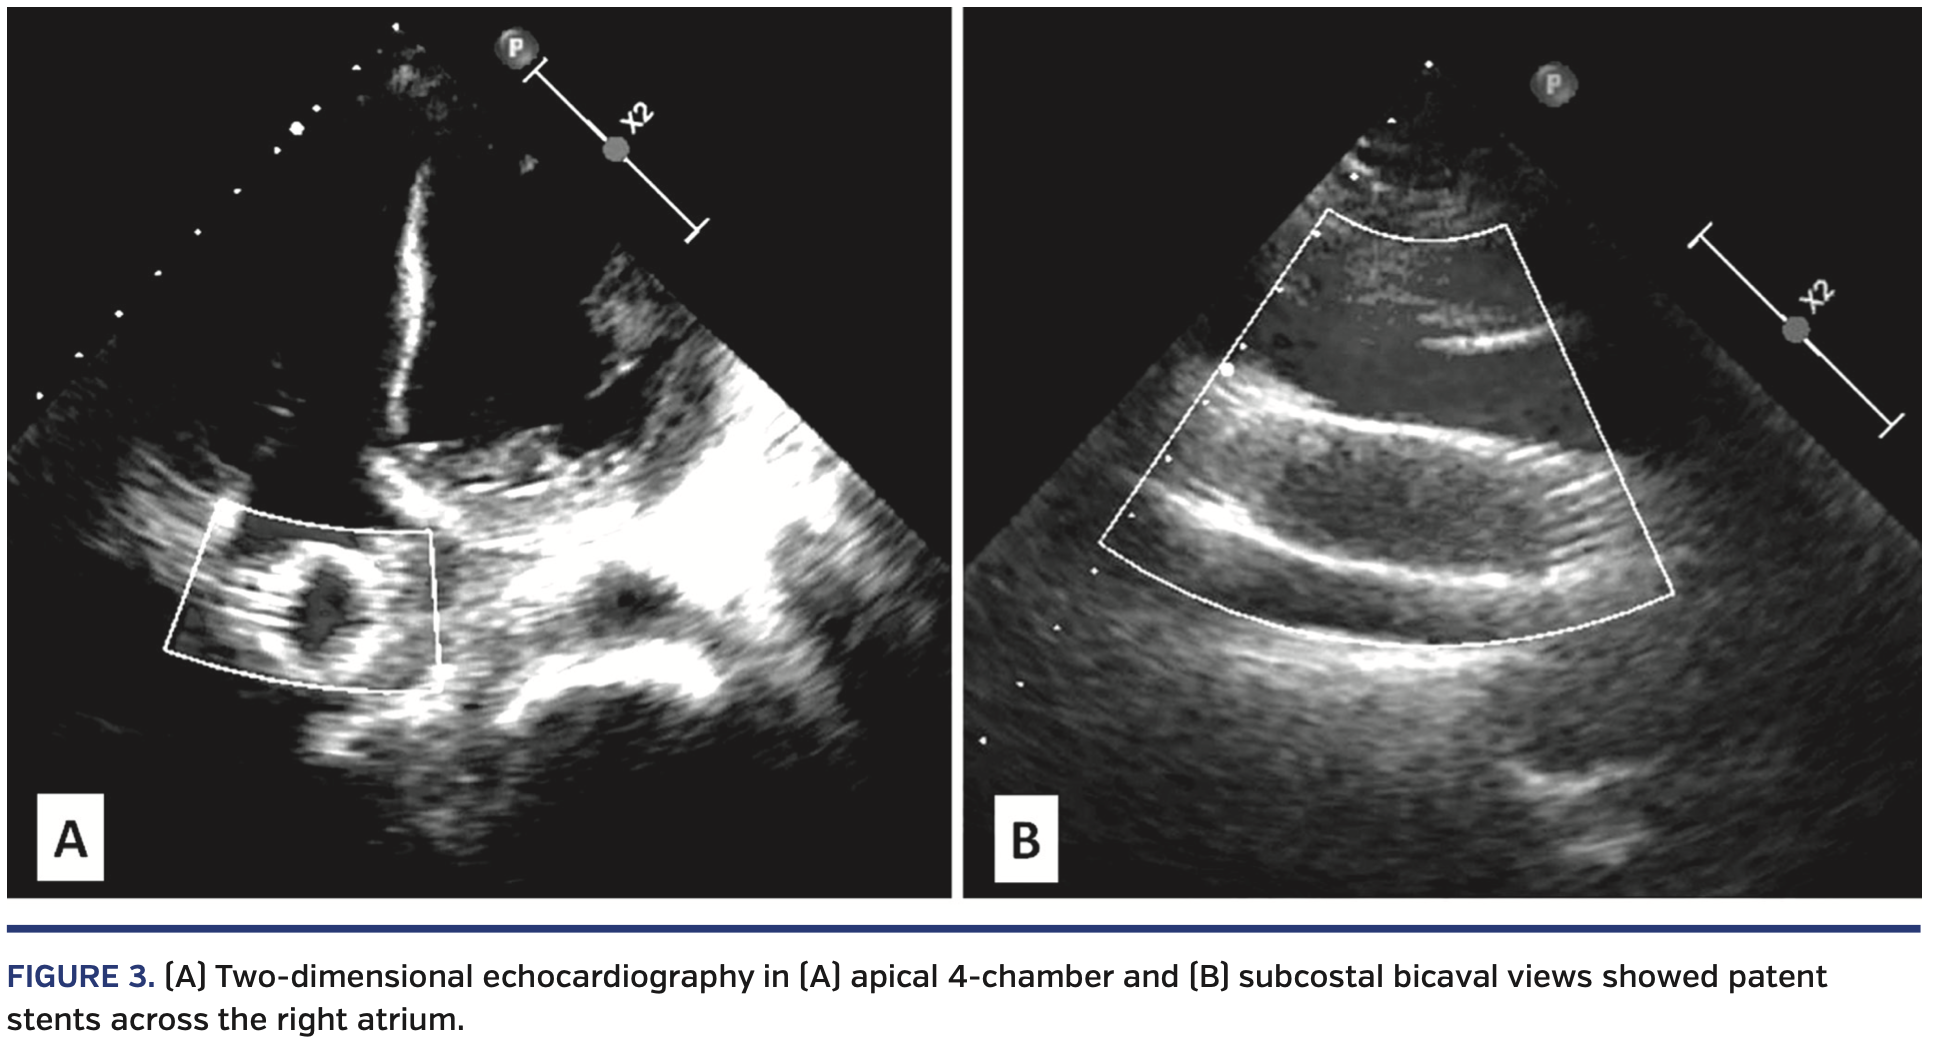

A 42-year-old female with end-stage chronic kidney disease, who was on maintenance hemodialysis for the last 3 years, presented with facial and upper-limb swelling of 2-month duration. As the 2-year-old right brachiocephalic fistula was not adequately functional, she was put on hemodialysis from the groin. Clinical examination revealed markedly engorged neck veins (Figure 1A). A computed tomography (CT) scan confirmed significant stenosis of the superior vena cava (SVC) (Figure 2A). She underwent percutaneous stenting of the SVC with a 16 x 60 mm self-expanding Wallstent (Boston Scientific) at an outside hospital. In view of persistent symptoms of SVC obstruction and migration of the Wallstent into the right atrium (Figure 2B), she was referred to our center for further management. Following discussion in a multidisciplinary meeting, it was proposed to perform a repeat endovascular intervention to relieve the SVC obstruction and manage the migrated stent. Following insertion of an 11 Fr right femoral venous sheath, a 0.032˝ hydrophilic wire (Terumo Medical) was placed in the SVC through the lumen of the migrated right atrial stent. The stenosed SVC segment was dilated with a 14 x 40 mm Atlas balloon (Bard Peripheral Vascular) (Figure 2C). A 24 x 100 mm self-expanding Sinus XL non-graft stent (OptiMed Medizinische Instrumente) was deployed, extending from the SVC to the inferior vena cava, through the migrated right atrial stent using the bridging-stent technique (Figures 2D and 2E). The SVC segment was further dilated with a 16 x 40 mm Atlas balloon. A brisk flow was achieved through the SVC (Video 1). Post intervention, hemodialysis could be restarted from the right forearm. At 6-month follow-up exam, she had marked improvement in her neck veins (Figure 1B), and two-dimensional echocardiography could delineate the well-positioned, tunneled stents across the right atrium (Figure 3).